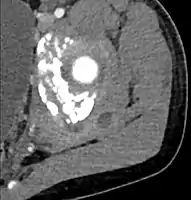

CT with IV contrast showing enlargement and heterogeneous hypodensity in the right pectoralis major muscle. A focal abscess collection with gas within it is present medially. There are enlarged axillary lymph nodes and some extension into the right hemithorax. Note the soft tissue and phlegmon surrounding the right internal mammary artery and vein. The patient was HIV+ and the pyomyositis is believed to be due to direct inoculation of the muscle related to parenteral drug abuse. The patient admitted to being a "pocket shooter"

CT exam showing a multiloculated fluid collection in the left gluteus minimus muscle found to be a staph aureus pyomyositis in a 12-year-old healthy boy.